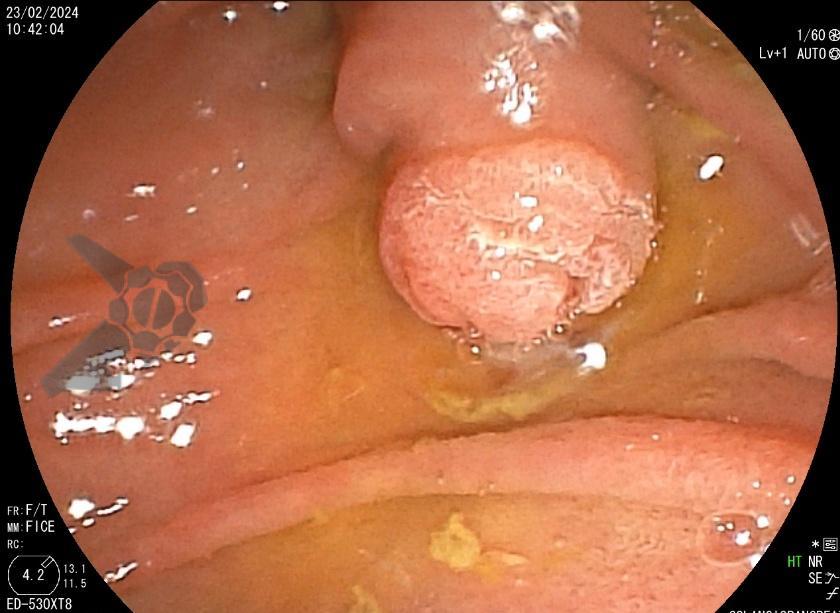

Dessa forma, indicada papilectomia endoscópica e realizada ressecção em monobloco, em modo endocut Q, sem injeção de submucosa. Não foi realizada esfincterotomia ou passagem de prótese biliar ou pancreática. Observou-se pequeno sangramento imediato no leito de ressecção, controlado com injeção de adrenalina. Não há lesão residual no leito. Paciente evoluiu bem, assintomática e sem intercorrências após o procedimento.

O anatomopatológico confirma biópsia prévia, com margens laterais e profundas livres de lesão (R0). Houve resolução da colestase após o procedimento: BT 0,98; BD 0,42; GGT 105; FAL 153. Paciente permaneceu sem lesões suspeitas no leito nos exames de seguimento, com biópsia após 1 ano exibindo apenas processo infamatório reacional.